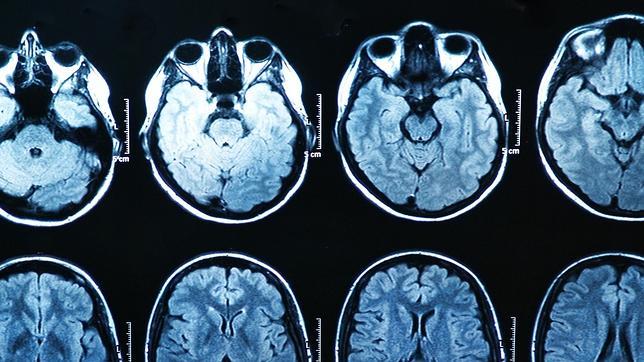

En la investigación, realizada por científicos del Instituto Max Planck de Berlín , los científicos analizaron la actividad cerebral de 64 hombres y la compararon con sus hábitos de consumo de pornografía. Y como resultado, descubrieron entre otras cosas que las personas qué pasaban más tiempo viendo porno tendían a tener un cuerpo estriado, una zona del cerebro relacionada con el placer y los circuitos de recompensa , más pequeño. Pero, ¿qué importancia tiene este cuerpo estriado? ¿Qué implica que sea más pequeña?

«Es una región muy bien conocida, muy importante para actividades relacionadas con recompensas», explica José Antonio Esteban García , un neurobiólogo del Centro de Biología Molecular Severo Ochoa de Madrid que trabaja en averiguar cómo funcionan en el cerebro los procesos relacionados con el aprendizaje y la memoria al nivel de las células. El cuerpo estriado «interviene en respuestas relacionadas con el placer, como el que se produce al comer o tener sexo, o con el consumo de drogas». ( Entrevista completa aquí ).

Y según explica, el hecho de que esta región se haga más pequeña no es necesariamente negativo: «Cuando una estructura cambia de tamaño no significa que no funcione o que esté atrofiada. Cuanto mejores nos volvemos en realizar una tarea concreta, en general necesitamos menos activación del cerebro, porque se refuerzan conexiones útiles entre neuronas y te basta con ellas».

Y además, el cambio de tamaño o de conexiones entre neuronas no solo se produce por un consumo de pornografía excesivo. «El cerebro está cambiando continuamente. Es tremendamente plástico. Cambia después de tener sexo y después de recibir una lección de geografía». Es decir, que al igual que un músculo se fortalece por utilizarlo, las diversas regiones del cerebro también cambian con el uso, o desuso, que se le dan.

Esta capacidad de adaptación del cerebro se conoce como plasticidad sináptica , y ocurre entre otras cosas gracias a un gran conjunto de mecanismos celulares que se basan en la comunicación entre neuronas. Y son precisamente esos cambios en la conectividad entre las neuronas los que nos permiten aprendernos la letra de una canción, acordarnos de un recuerdo, cambiar nuestra forma de pensar u olvidar la cara del vecino...